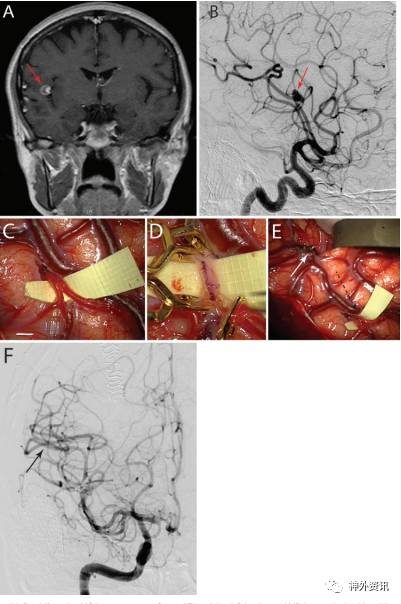

分叉处动脉瘤的治疗取决于动脉瘤的破裂情况(图2)。5例患者为分叉处动脉瘤,其中4例表现为蛛网膜下腔出血(SAH)。处理MCA分叉处动脉瘤,并行搭桥术(图5)。

图5. 分叉处动脉瘤。A.DSA显示MCA分叉处下干起源于动脉瘤基底,沿M1段走向;B.血管造影3D图像显示分叉上干也起源于大脑中动脉瘤的基底,向上走向;C.双重再移植血管搭桥术将分叉上干与血管移植段进行端侧吻合;D.再将移植段远端与分叉下干进行端侧吻合;E.动脉瘤完全孤立并切开;F-G.术后血管造影前后位和侧面观显示动脉瘤完全消失。